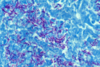

Dust particles in the alveoli are ingested by macrophages which then become “coal macules”

- 2-5mm radio-opaque nodules on CXR

- Nodular opacities occur primarily in the upper lung fields in simple version

- May become more widespread and then confluent with progression to large opacities in complicated version with progressive massive fibrosis

Pneumoconiosis – Coal Worker’s Lung